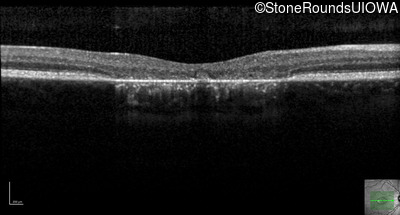

This 22 year old man had macular abnormalities noted incidentally at a routine eye exam at age 19. Since then, he has experienced a gradual loss of acuity particularly in the left eye.